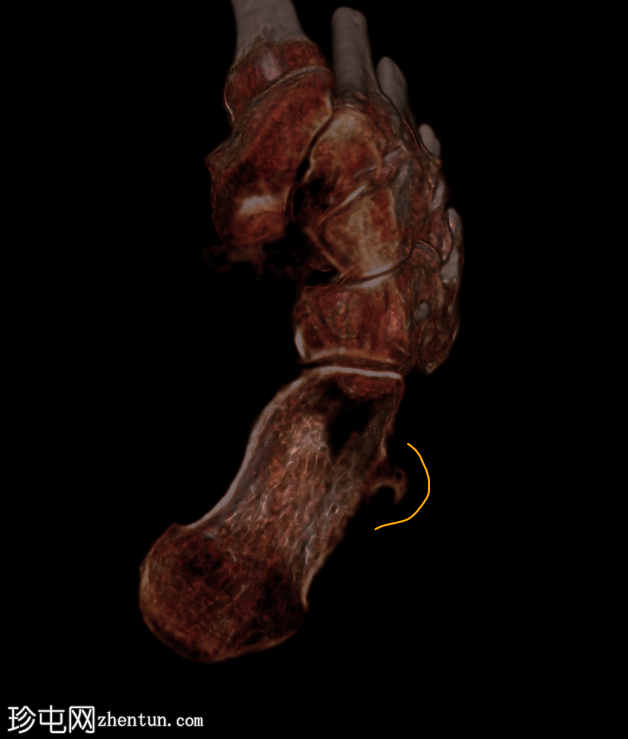

临床表现

跟骨外侧

疼痛

。

患者资料

年龄:65岁

性别:女

腓骨结节解剖图(带注释)

病例讨论